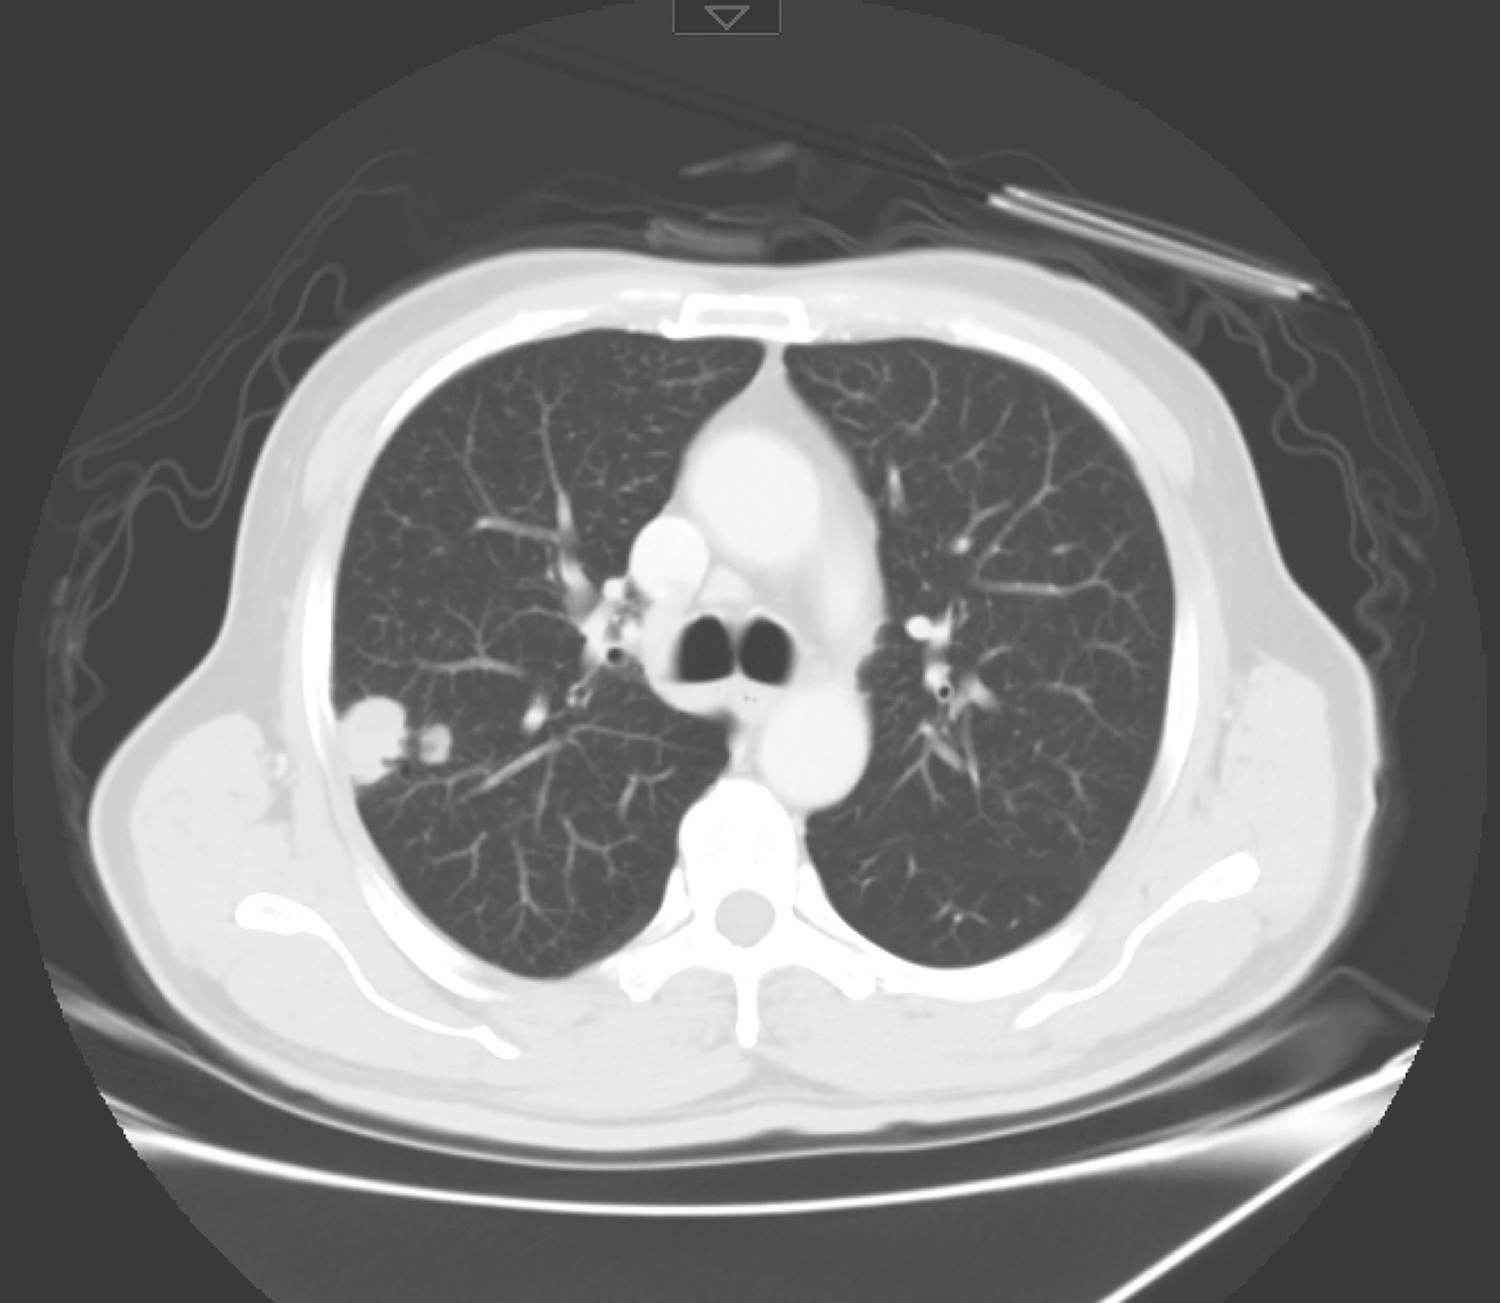

3.2016年11月28日颈胸部CT

检查所见:会厌根部局部略不均匀,舌根部见结节样不均匀强化,余咽喉未见明确肿物。双颈未见明确肿大淋巴结。右肺上叶后段结节,最大截面约1.4cm×1.0cm,边界尚清,边缘见少许毛刺及条索,周边见多个小结节(图2)。余肺未见明确结节或肿物。纵隔及肺门未见明确肿大淋巴结。未见胸腔积液、心包积液。

图2 右肺上叶后段结节

引自:头颈部肿瘤多学科诊疗病例精选.第1版.ISBN:978-7-117-27929-1.主编:李正江

影像学诊断:

(1)会厌根部局部略不均匀,请结合镜检。

(2)舌根部结节样不均匀强化,滤泡增生?请结合临床检查。

(3)右肺上叶后段病灶,考虑结核较肿瘤可能大,请结合临床。

7.2017年11月1日喉癌术后颈胸CT复查,参阅术前2016年11月28日CT图像,所见如下:

(5)右肺上叶后段多个结节较前增多、增大,部分融合成团,现大者最大截面约2.4cm×1.8cm(图5),需高度警惕恶性,转移瘤或原发肺癌待鉴别,请结合临床,建议活检。余双肺可见多发小结节,部分为新出现,大者约0.4cm,转移瘤可能性大。

图5 右肺上叶后段多个结节较前增多、增大

(6)纵隔见多个淋巴结,较大者约0.9cm。

(7)双侧胸腔及心包未见积液。